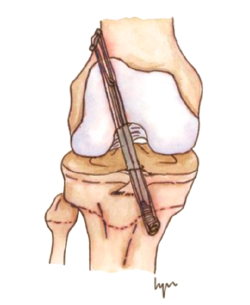

La resonancia magnética es el método de elección para el diagnóstico, con una sensibilidad del 95% y una especificad del 88% para las lesiones del LCA en la edad pediátrica(59). También mostrará, con alto grado de fiabilidad, la presencia de lesiones concomitantes, meniscales y condrales(60)(Figura 2).

Figura 2. Resonancia magnética de rodilla (A: T1/B: T2) de un paciente de 6 años con rotura completa del ligamento cruzado anterior.